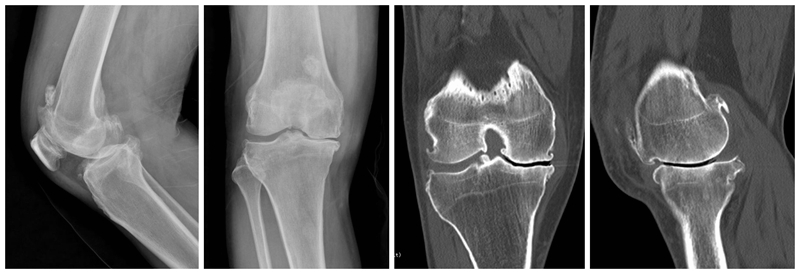

合并ACLD的单髁置换术

术前

术后检查

ACL损伤是否适合单髁置换,争议较大。需要鉴别原发韧带损伤继发OA还是原发OA继发ACL损伤。前者一般年龄轻,运动量大,适合一期或二期UKA联合ACL重建,后者一般年龄偏大,运动量少,需要术前详细评估膝关节稳定性。UKA仍是治疗内外不稳定的一种选择,而前后不稳定应探索其他治疗方案。髁间窝骨赘作为膝关节二级静态稳定结构。手术中引起撞击或磨损的骨赘要完全去除,其它骨赘建议保留。必须保留所有残留的ACL。适度减少胫骨后倾,一般应小于5°。